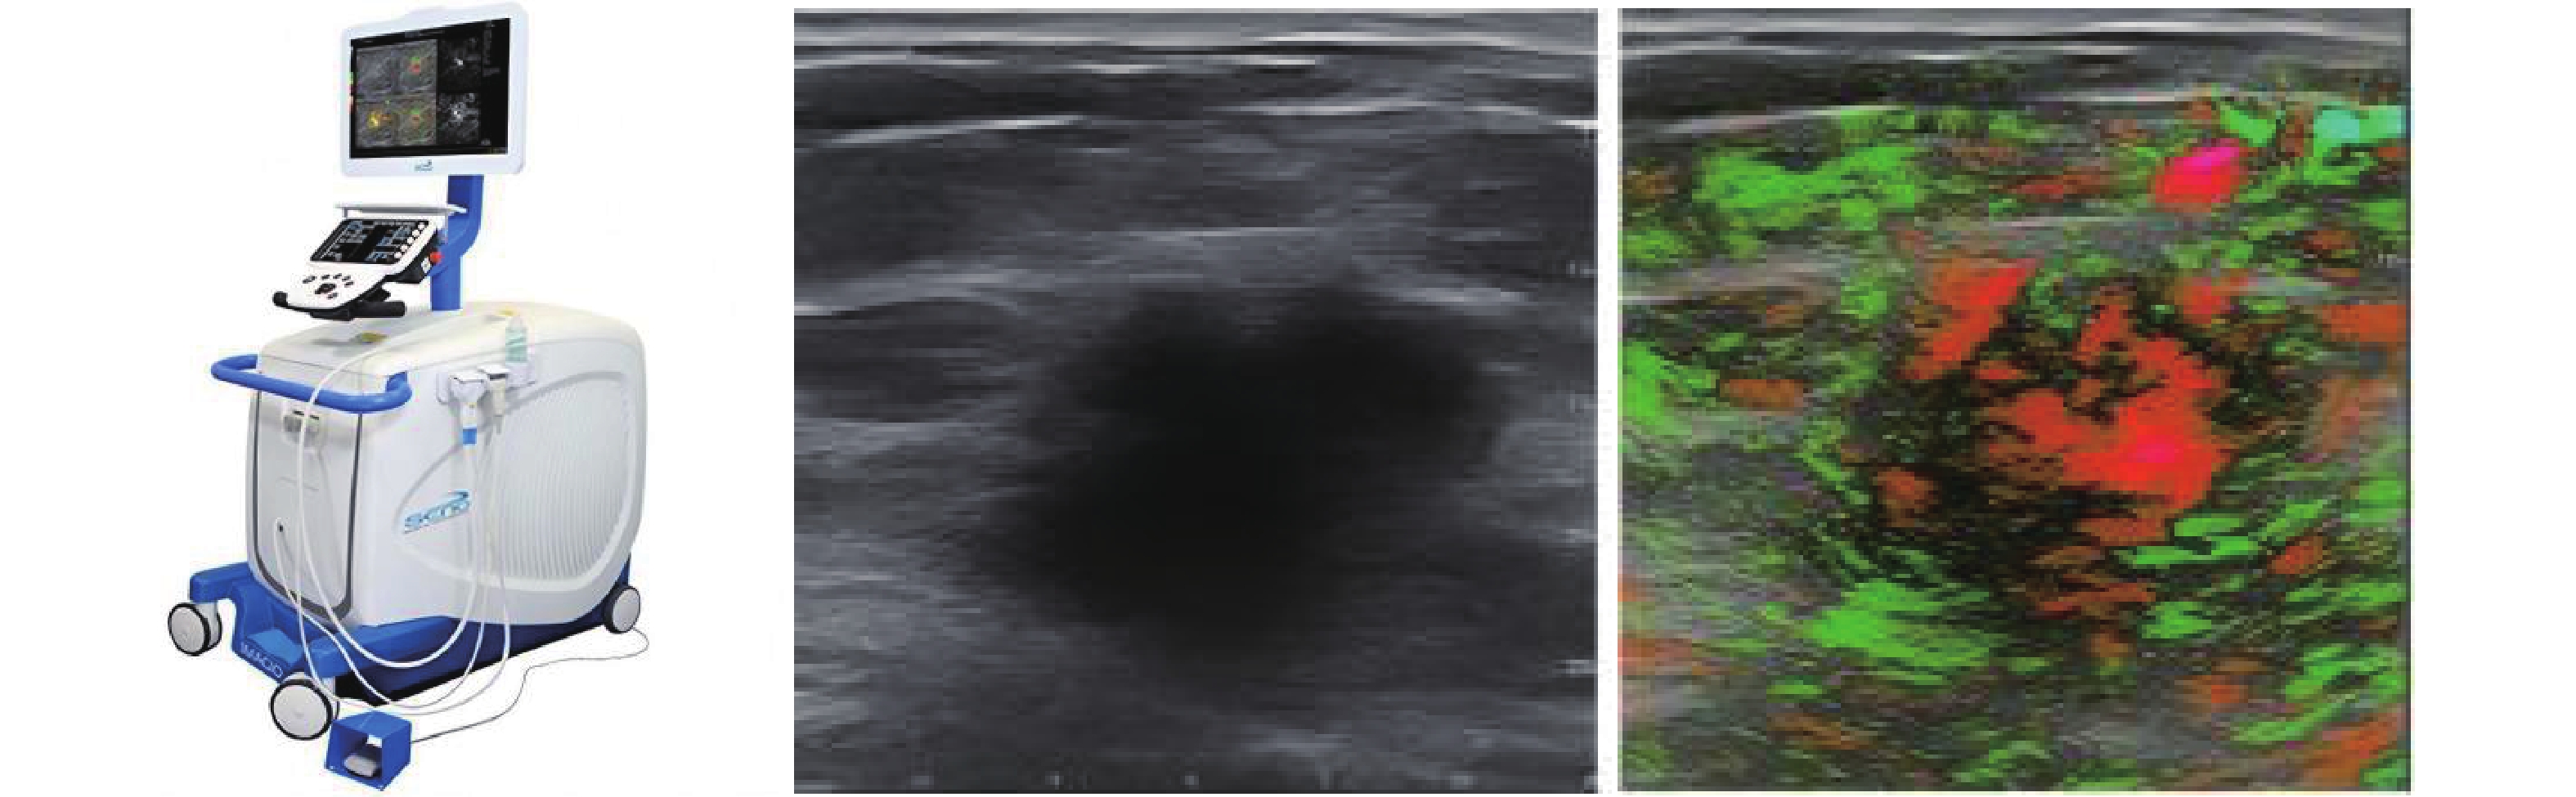

Figure 3

3D PA/US reconstructions of vascular networks in (A) an invasive breast cancer and (B) a breast fibroadenoma. Malignant tumors demonstrate dense peripheral vasculature and sparse central perfusion, whereas benign lesions exhibit more uniform vascular distribution. The probability density distribution of SO2 in the (C) intratumoral and (D) peritumoral regions further illustrates that malignant tumors have lower SO2 compared with benign counterparts [14]."